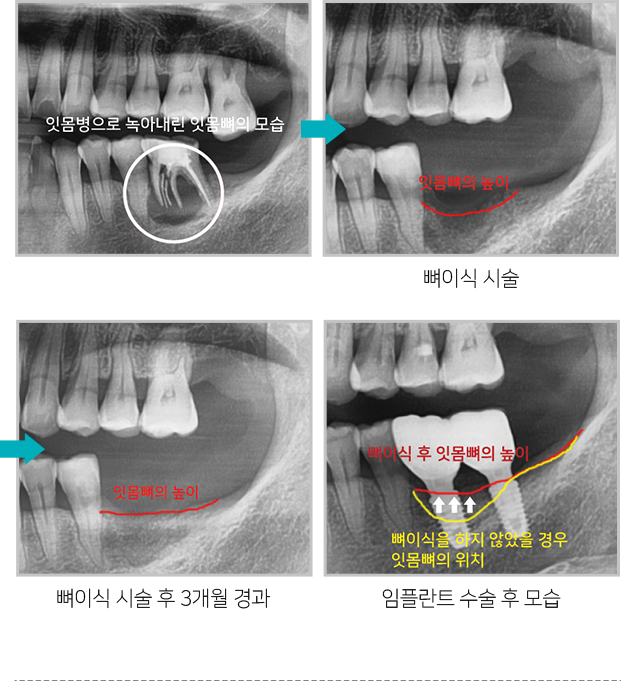

치조골은 치아를 발치 한 후 지속적으로 녹아

없어지는데 치조골을 보존하기 위해

발치 후

미리 뼈이식 하면 추후 임플란트 식립시 충분한

치조골을 확보할 수 있어

임플란트 수술을 하는데

매우 유리합니다.

뼈이식 시술 후 잇몸뼈의 위치 변화